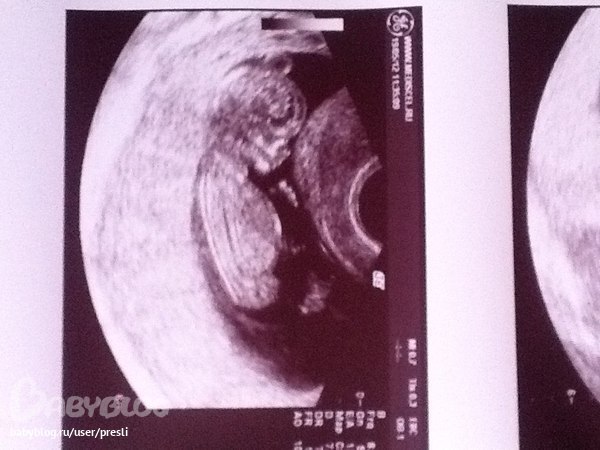

На втором скрининг фото малышки, и вес был уже 400г))

Пиночки заметные довольно, лежит в головном, довольно активная. Просыпается после моего приема пищи) Очень активно копошится, когда я за рулем-не нравится ей что-ли ☺️ Мне кажется или икать уже начала... не помню на каком это сроке начинается...

А и еще профиль конечно со старшей очень разный

Слева старшая дочка, носик у нее кругленький такой. Вот еще старшая, моя красавица))